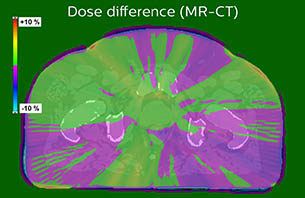

We felt comfortable doing that because we were using thresholds in the dose calculation comparisons – for the planning treatment volumes PTV mean and PTV median – that were set to 2%. We very rarely went over 1% and the average difference in PTV mean values was 0.8% for all 62 patients in the dose comparison. In short, the dose differences between MRCAT- and CT- based radiotherapy plans were minimal. That was a really good sign for us to trust MR-only simulation in the third phase.”

Based on the 3D T1W mDIXON images, MR-based density maps (MRCAT) are automatically generated. The VMAT (Volumetric Modulated Arc Therapy) plan is generated in TPS, based on MRCAT as primary image set. During the commissioning phase, dosimetric agreement between MRCAT-based and CT-based dose plans was studied and differences in the PTV dose were found to be minimal (<1% for most patients). Average difference in PTV mean values was 0.8% over the study group (n=62).